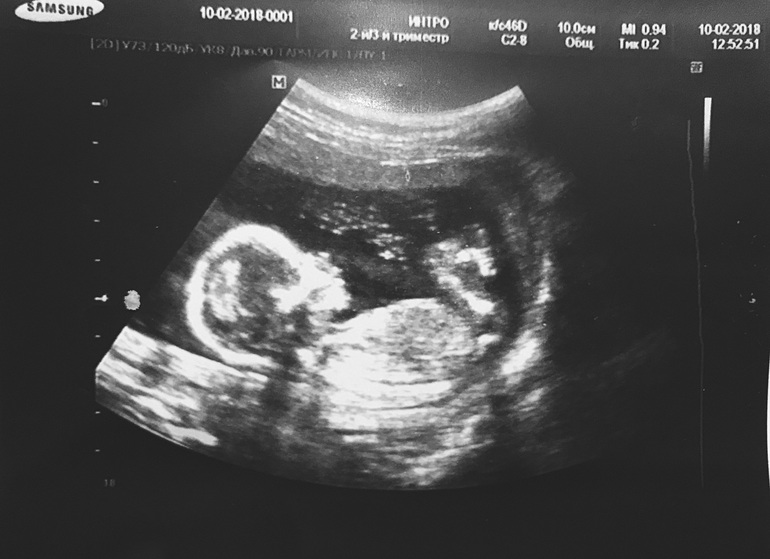

Половой бугорок. Мальчик или девочка?

УЗИ, КТГ, доплерДевочки, кто разбирается, скажите, кто же поселился в домике?) Один врач предположил девочку, второй мальчика)) интрига))) срок 15 недель

Девочка однозначно, бугорок ниже 30 градусов от туловища.По второй фотке отчетливо это видно)